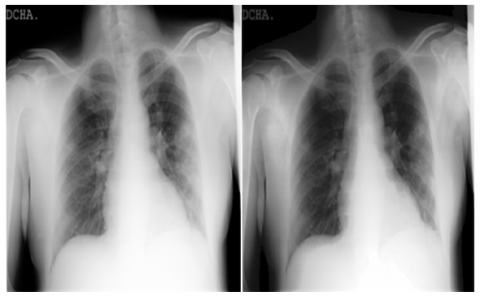

Together with collaborators from Pakistan and Malaysia, a research team from Qatar University in Doha, Qatar, and the University of Dhaka in Bangladesh has created a database of chest X-ray images for COVID-19-positive patients as well as photos of typical and viral pneumonia. This dataset of COVID-19, normal, and other lung infections is being provided in phases. Table 2 shows the details of the COVID-19 Radiography Dataset. Some COVID and Normal patients’ CXR images of this dataset are shown in Figure 3 to Figure 6.

The normal chest X-ray shows clean lungs with no spots of aberrant opacification. Lung opacity is characterized by a localized lobar consolidation, in this case in the right upper lobe (white arrows), whereas viral pneumonia is characterized by a more widespread “interstitial” pattern in both lungs. Pictures that do not meet the aforementioned characteristics are classified as having COVID-19 disease.

Figure 3. Normal CXR image example from the COVID-19 Radiography Database

Figure 4. COVID CXR image example from the COVID-19 Radiography Database

Figure 5. Viral Pneumonia CXR image example from the COVID-19 Radiography Database

Figure 6. Lung Opacity CXR image example from the COVID-19 Radiography Database